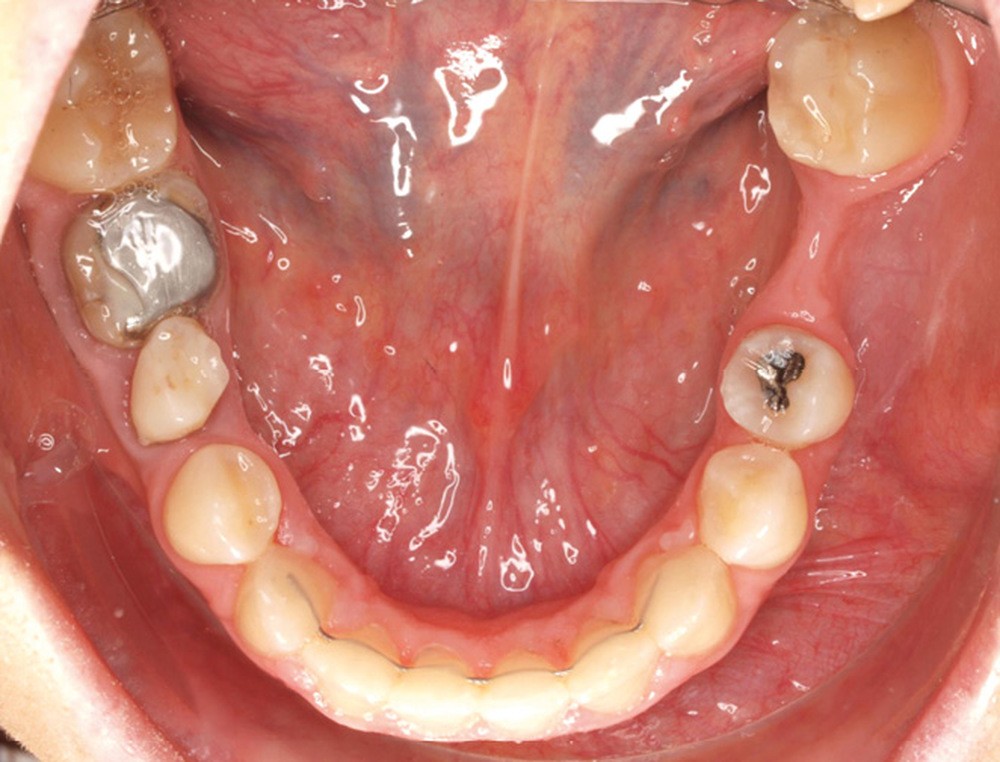

Diagnostic (fig. 1a-g)

La patiente présente une classe III squelettique dans un contexte hyperdivergent associée à une endoalvéolie maxillaire, un articulé inversé antérieur, une rétroversion incisive maxillaire, des rapports de classe I canine bilatérale, une absence de 16 et 36.

Au niveau esthétique, le profil est rectiligne. La lèvre supérieure est plus effacée, en retrait par rapport à la lèvre inférieure. De face et de profil, la mandibule paraît massive et le maxillaire effacé : le manque de soutien de la lèvre supérieure contribue à cette impression.

Le sourire est étroit, dégradé par les malpositions dentaires.

Au niveau fonctionnel, il existe un pro-glissement mandibulaire et un articulé inversé antérieur. Le profil téléradiographique montre en occlusion des rapports labiaux et un profil de classe III plus marqué que sur photographies.